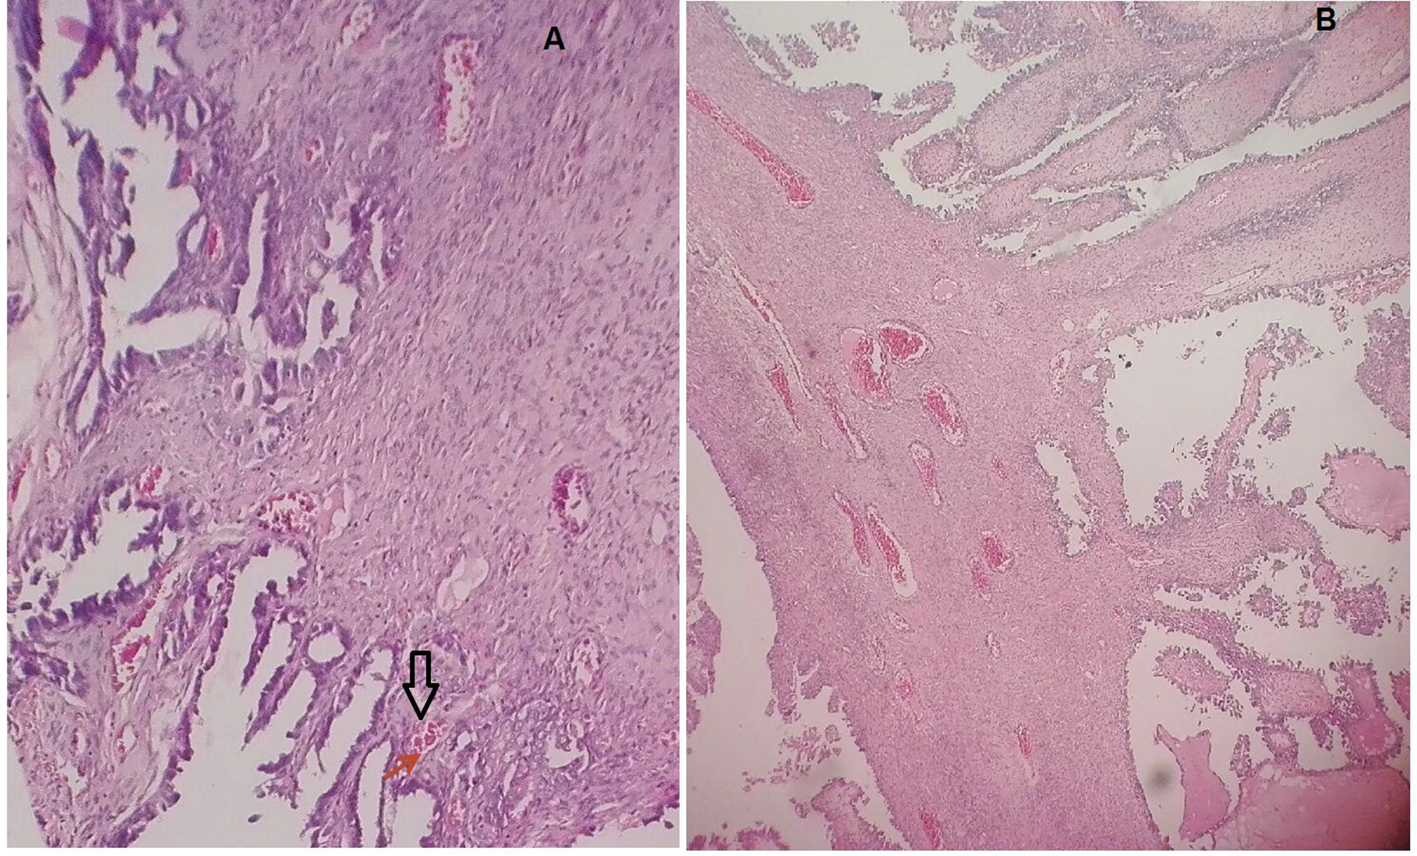

A total of 160 patients with early stage EC were identified. Out of 160 women with EC, 135 (84.4%) underwent primary surgery. Endometrioid cell type histology was the most common cell type comprising 75.5% (120 patients), followed by serous, clear cell carcinoma and adeno-squamous cell type, respectively (Table 1). Figure 1 illustrates a case of LVSI compared to the normal subject. One hundred and twenty-one (76.2%) patients were not found to have LVSI, where 38 (23.8%) were found to have LVSI. Of the 38 patients with LVSI, 21 (55.3%) had endometrioid cell type tumor, 10 (26.3%) had serous, one (2.6%) had clear cell and six (15.8%) had adeno-squamous cell type tumor. Eighty-seven patients received adjuvant radiation therapy, of whom 24 (27.6%) presented LVSI, and 63 (72.4%) were not found to have LVSI.

![]() Click for large image | Figure 1. A case of LVSI compared to the normal subject. |